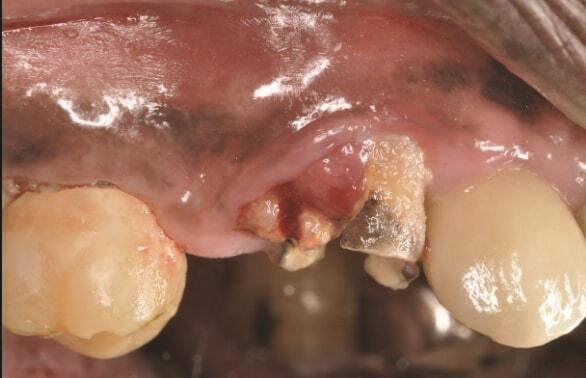

Пациент 2: Здоровый пациент мужского пола 63 лет обратился с имплантатом № 1.3, у которого диагностирован РПИ, на который повлиял ранее эндодонтически леченный и сломанный зуб № 1.4 (Фото 3 и Фото 4). Глубина зондирования вокруг имплантата составляла от 4 до 10 мм (Таблица 1), причем наиболее серьезная потеря кости наблюдалась с дистальной стороны имплантата № 1.3 (Фото 3 и Фото 4).

Фото 3 и Фото 4. Случай 2: Первоначальная клиническая картина, показывающая имплантат № 1.3 с РПИ, на который повлиял сломанный зуб № 1.4 (Фото 3); рентгеновский снимок, показывающий сломанный зуб № 1.4 с периапикальным поражением, распространяющимся на дистальную сторону имплантата № 1.3 (Фото 4).